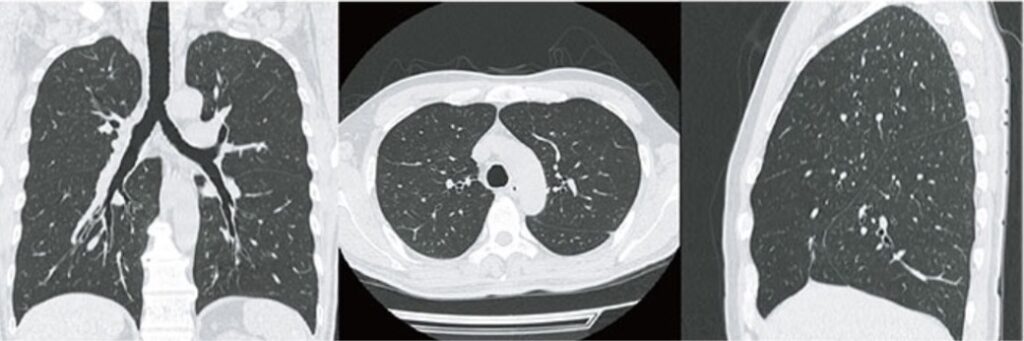

CT検査による画像

上記レントゲンと同じく胸部をCT検査した場合の画像です。三次元にて任意断面での診断が可能です。

胸部のCT検査では、肺がん、肺炎、気胸、胸部⼤動脈瘤、⼼臓疾患などの病変が発⾒されやすいです。腹部のCT検査では、肝臓、胆嚢、膵臓、腎臓、脾臓‧⼩腸‧⼤腸などを調べますので、腹部の臓器に発症するがんや炎症を疑うことができます。